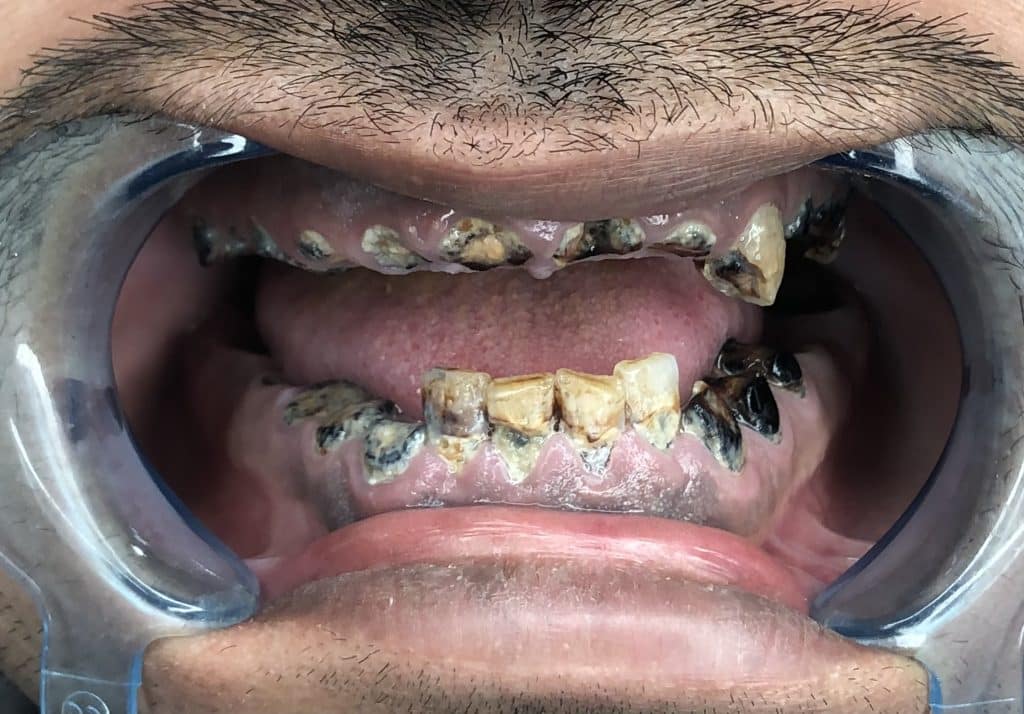

Patient’s assessment :

The patient is 33 years old , business man , married and has a children .

The diagnostic aid : panoramic x-ray , clinical examination .

Gingival diagnosis : there is no inflammation in the ligaments .